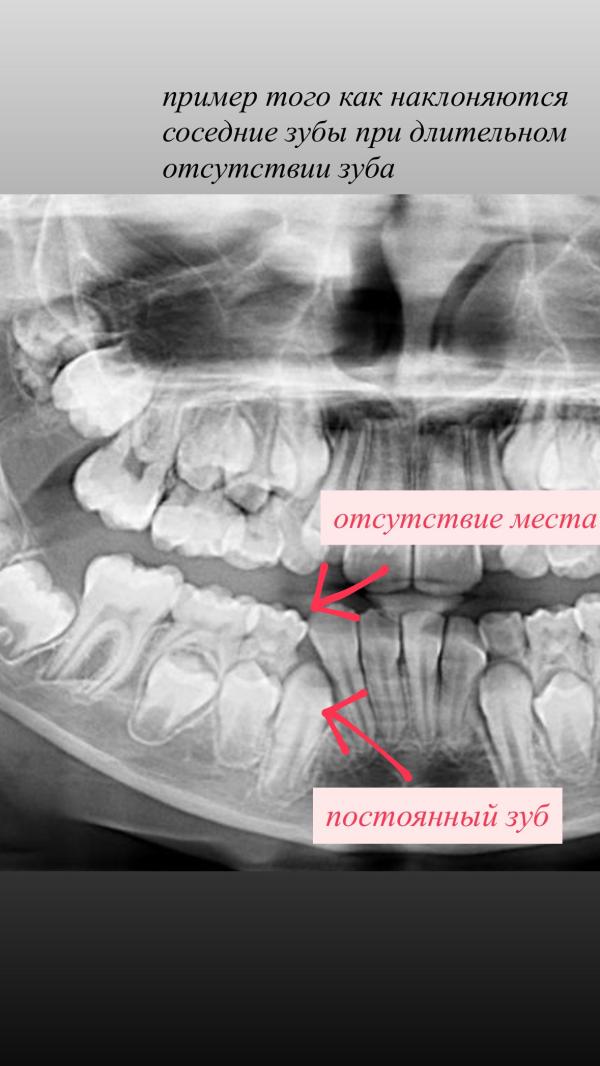

Удерживать место после удаления❗️

В таких случаях изготавливаем съемные пластинки с зубами, 1. будет удерживать место, 2.ребенок полноценно и эффективно будет жевать, 3. стимуляция роста постоянных зубов